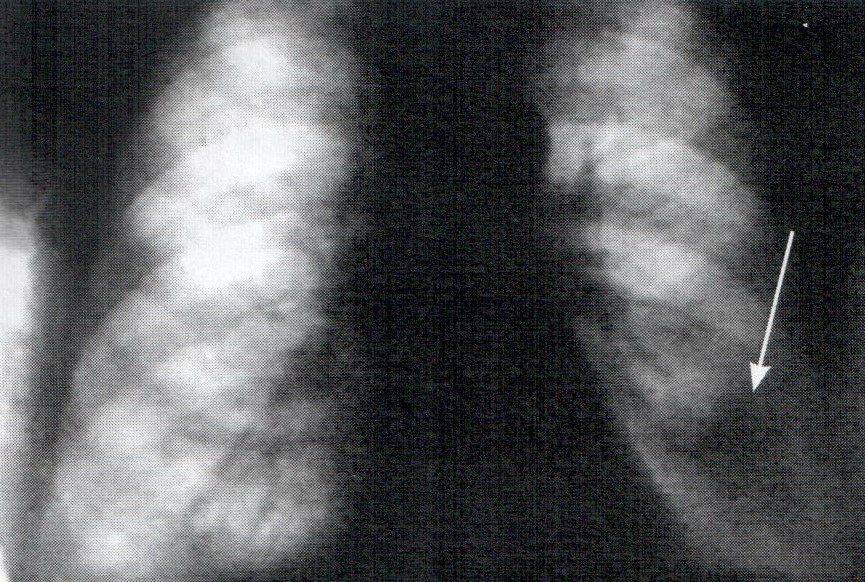

Выполнен экстренный эндоскопический гемостаз — криовоздействие хлорэтилом. Биопсия: признаки хронической язвы. Томограммы и рентгенограммы легких: периферический рак нижней доли левого легкого (рис. 10).